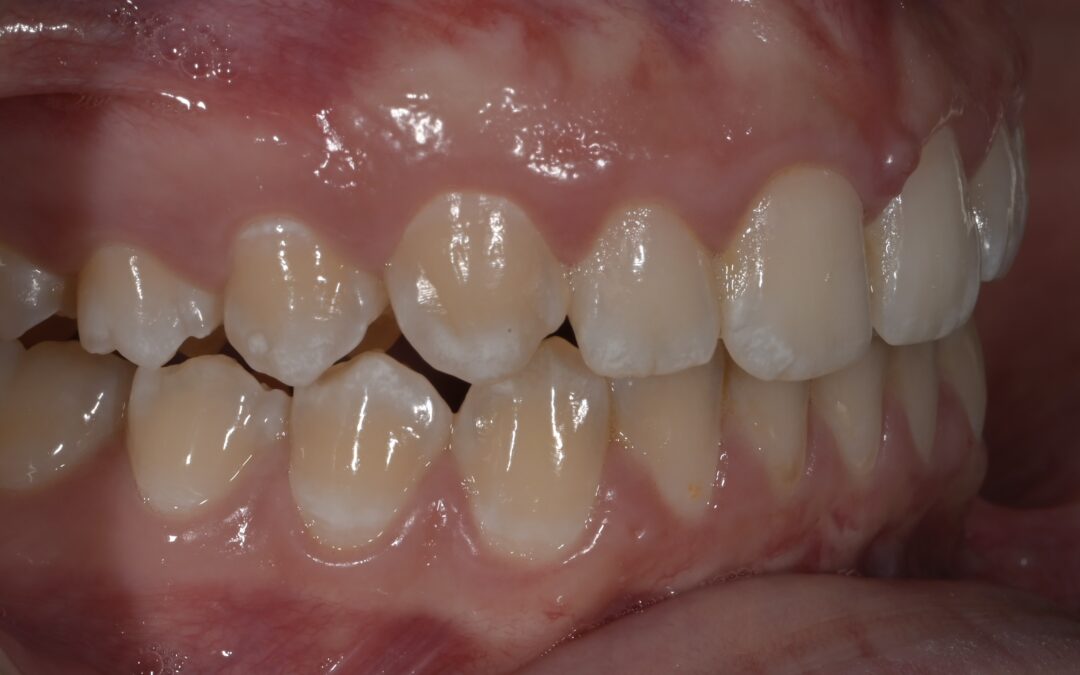

ORTODONZIA. Terapia funzionale e fissa per allineamento dentale

Paziente 10 anni, overjet aumentato, II classe con palato contratto, affollamento dentale e deviazione della linea mediana Terapia: • Prima fase: terapia Intercettiva con espansione del palato, durata 12 mesi • Seconda fase: terapia fissa con estrazione dei premolari,...